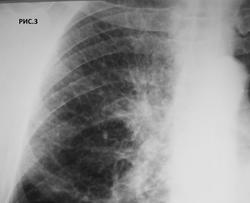

Больной 63, крановщик, курильщик. Перенес левостороннюю пневмонию 15.12.2010 (рис.1). В течение 10 дней до рентгенографии грудной клетки от 1.4.2011 (рис.2.3.4) беспокоит сухой кашель. Температура тела нормальная. С уважением Nikolas

думается то что называют повышенной прозрачностью - нормальная ткань, а вот верхняя гиповентилируется, жаль на боковом не все четко как хотелось бы...или какаято неоднородная инфильтрация  есть и вдоль междолевых...а может это уже фантазии..

Смею высказаться за диффузный пневмофиброз, корни  фиброзно изменены. правый корень кажется "пушистым" за счет вышесказанной ассиметрии укладки. Теней подозрительных на увеличенные лимфоузлы в проекции корней не отмечается. Ну про разность пневмотизации легочных полей так же выше сказано. Вообщем пока ХОБЛ .